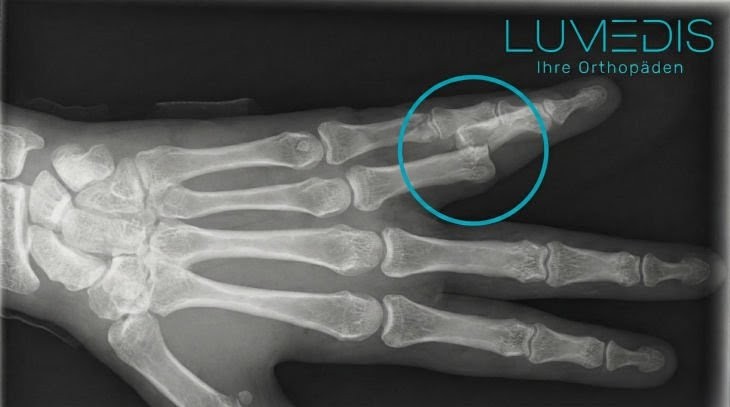

So sieht ein gebrochener Daumen im Röntgenbildaus:

Röntgenbild eines gebrochenen Ringfingers (Nagelkranzfraktur)

Röntgenbild eines gebrochenen Fingers von der Seite